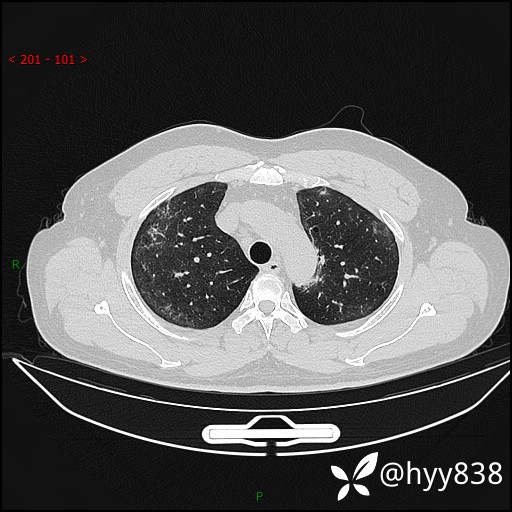

第一次胸部CT